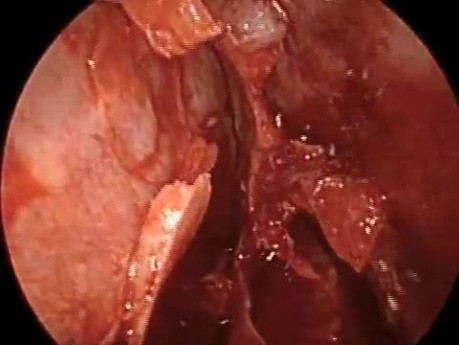

Dwie przyczyny obstrukcji nosa i metody leczenia...

Najczęstszymi przyczynami obstrukcji nosa są: skrzywienie przegrody i przerost migdałków. Wideo przedstawia plastykę przegrody oraz przeznosowe usunięcie powiększonych migdałków.